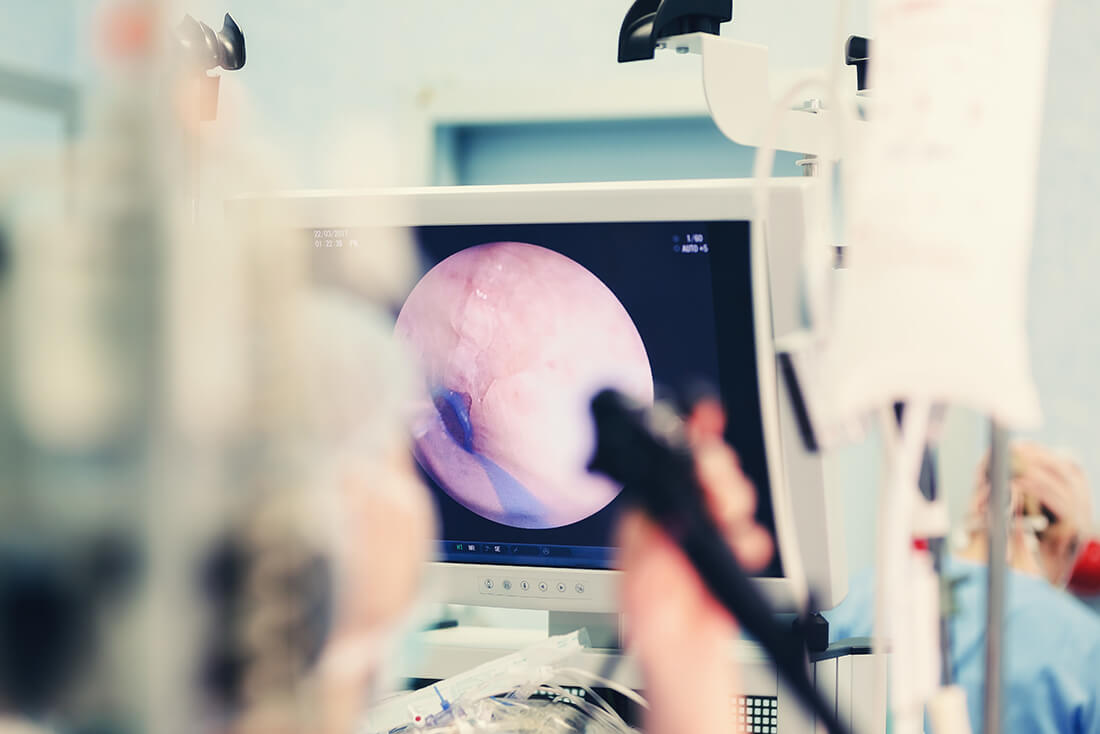

Providing Flexible Endoscopy Solutions for NHS Trusts

Your Medical Services offers tailored Endoscopy Services to support NHS Trusts in managing the increasing demand for endoscopic care. Our flexible solutions cover Outpatient, Diagnostic, and Surgical pathways, providing full pathway support or targeted assistance to relieve pressure at specific points. We ensure that our services integrate seamlessly with the Trust’s existing infrastructure and resources, optimising patient care and helping Trusts manage capacity more effectively.

• Diagnostic Endoscopy: Enhancing Trust capacity for essential endoscopic procedures, including colonoscopies, gastroscopies, and sigmoidoscopies. Our skilled Endoscopists and Specialist Nurses ensure that diagnostic assessments meet the highest standards of care, reducing waiting times for critical diagnostic services.

• Therapeutic Endoscopy: Providing expert support for therapeutic procedures such as polypectomies, dilations, and stenting. This ensures that Trusts can manage both diagnostic and treatment backlogs, offering timely interventions for patients in need of therapeutic care.